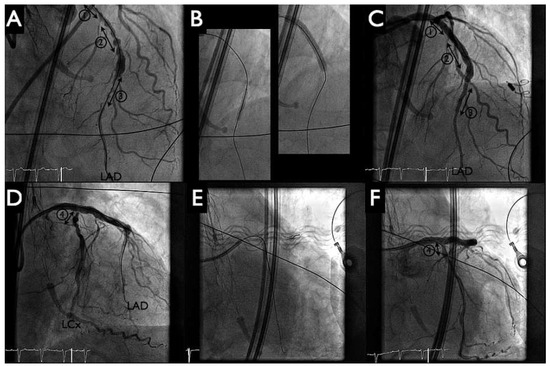

HeartMate PHP Axial Pump for High-Risk PCI

by Diego Arroyo, Serban Puricel, Mario Togni and Stéphane Cook

Cardiovasc. Med. 2016, 19(9), 241; https://doi.org/10.4414/cvm.2016.00430 - 21 Sep 2016

Percutaneous left ventricular assist devices (pVADs) can provide temporary circulatory support during high-risk percutaneous coronary interventions (PCIs). We describe the first case in Switzerland of high-risk PCI with a new pVAD, the HeartMate PHP axial pump (St Jude Medical). Full article